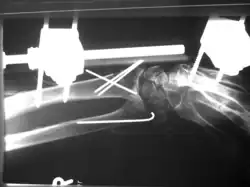

Aufgrund der Biegsamkeit der Drähte und der nicht formschlüssigen Verankerung der Drähte im Knochen ist das Operationsergebnis in der Regel nicht bewegungsstabil, sodass weitere Ruhigstellungsverfahren, z. B. Gipsverband oder auch der hier illustrierte Fixateur externe zur Anwendung kommen müssen.

Bei der hier dargestellten Handgelenkfraktur war eine bewegungsstabile Versorgung z. B. mittels winkelstabiler Platte (s. u.) aufgrund der hochgradigen Osteoporose und der erheblichen Weichteilschädigung nicht sinnvoll, daher erfolgte die geschlossene Reposition mit Kirschnerdraht-Fixierung und zusätzliche Ruhigstellung mit Fixateur externe. Eine Gipsruhigstellung wäre hier ebenfalls aufgrund der schlechten Weichteilverhältnisse nicht möglich gewesen.

Vorteil der Kirschnerdraht-Fixierung ist der geringe Verfahrensaufwand und die geringe Invasivität. Die Entfernung der Drähte erfolgt in der Regel unmittelbar nach Abschluss der Frakturheilung (also nach ca. 4 bis 6 Wochen).